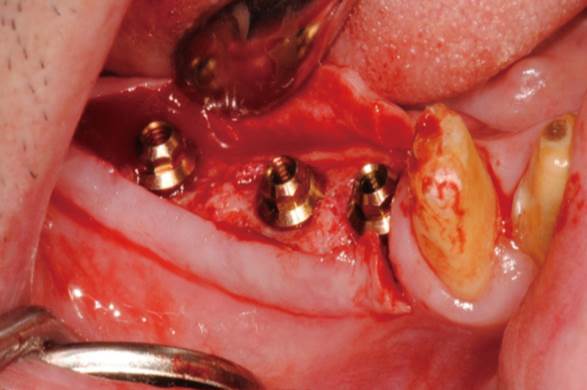

Clinical case: Extraction of all teeth in upper maxilla,

immediate implant placement, & provisionalization

- Courtesy of Dr. Iulian Filipov, Romania -

Keywords

AnyRidge, immediate placement, immediate provisionalization, maxillary fully edentulous case, initial stability, edentulous, Dr. Iulian Filipov, R2GATE, MEGA ISQ